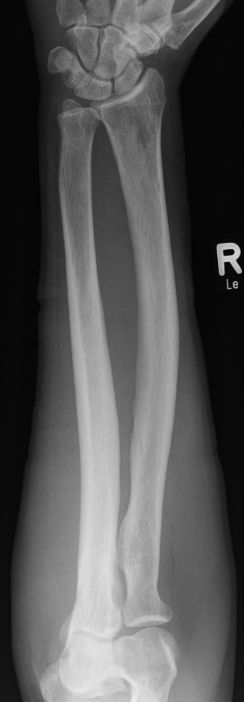

| Ulna | 56-jähriger Mann mit Plattenepithelkarzinom des rechten Hauptbronchus T4 N2 M1. Schmerzhafte Schwellung an der Innenseite des rechten proximalen Unterarms. Deutliche Sklerosierung der Ulna.

![]() |